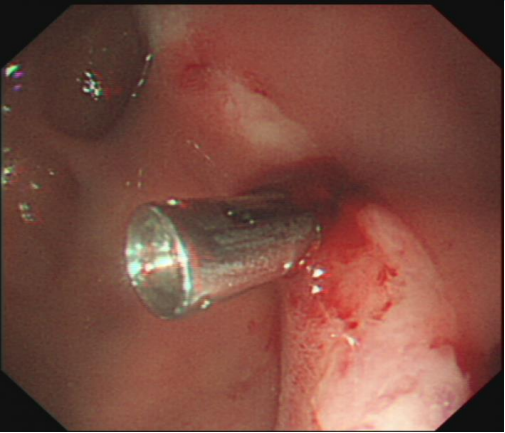

Esophagogastroduodenoscopy showed a juxtapapillary thin-walled diverticulum in the descending segment of duodenum with a ulcerative lesion oozing in its edge (Figure 1B).

Figure 1: Abdominal computed tomography revealed a large intraluminal diverticulum located in the descending duodenum after initial fluid resuscitation. B. Esophagogastroduodenoscopy showed a juxtapapillary thin-walled diverticulum in the descending segment of duodenum with a ulcerative lesion oozing in its edge.

An over-the-scope clip was successfully deployed after attempted hemostasis with adrenalin failed. The patient experienced an uneventful clinical course. Diverticular bleeding is an rare cause of upper gastrointestinal bleeding [1]. Most duodenal diverticula are located on the second part of the duodenum, originated from a congenital malformation of the descending duodenum, which may lead to epigastric pain, vomiting, or bleeding depending on size and the relationship to the papilla of Vater [2]. Symptomatic bleeding from a duodenal diverticulum is uncommon. Sclerotherapy, mechanical, and thermal devices are useful for successful management of diverticular bleeding by endoscopy [3] .